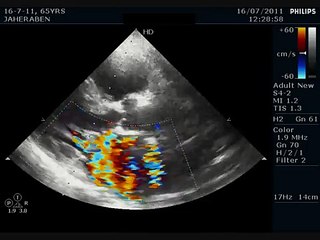

HOCM WITH Systolic anterior Motion of Mitral Leaflet

Hypertrophic obstructive cardiomyopathy with systolic anterior motion of the anterior mitral valve. Illustrated using flash and static animation. The best example of HOCM with SAM I have seen. You can also subscribe to us atm- .